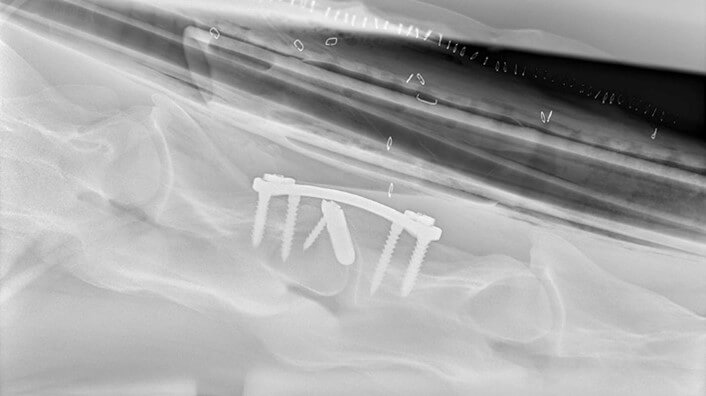

Während der Operation wird das Pferd anästhesiert und in einer chirurgischen Hängematte immobilisiert. Eine mit dem 3D-Drucker hergestellte Platte und 3D-gedruckte Spongiosaschrauben stabilisieren den Bruch und überbrücken die Wirbel. Abhängig von den betroffenen Wirbeln wird im ventralen Bandscheibenbereich ein kleiner 3D-gedruckter Cage aus Titan eingesetzt.

Zusammenspiel von Schrauben und 3D-Druck-Platte

Die Form der Platte ermöglicht die Platzierung der drei Schrauben in jedem Wirbel. Titan-Implantate ermöglichen eine bessere Osseointegration als Stahlimplantate. Mit dem Metall-3D-Druck können poröse Strukturen angefertigt werden, die das durch den Cage hindurch und die Fixierung des Knochens am Cage erleichtern.

Die eingesetzten Schrauben sind selbstschneidend und teils selbstbohrend, was in der Nähe des Markkanals eine maximale Verankerung zulässt und die Gefahr der Perforation beim Bohren und Schneiden reduziert. Das Risiko lässt sich Rossignol zufolge mit einer Redondrainage begrenzen. Kommt es zum Lösen oder Herausziehen der Schrauben, ist das eher ein technischer Fehler oder mangelhafter Kontakt der Platte zur Knochenoberfläche.